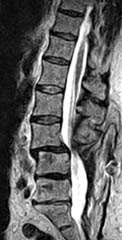

Cervical Spine |

|

Upright Neutral |

Upright Extension |

Unsuspected

Disc Herniation in Extension |

Lumbar Spine |

Recumbent, Weightless |

Upright, Weight-Bearing |